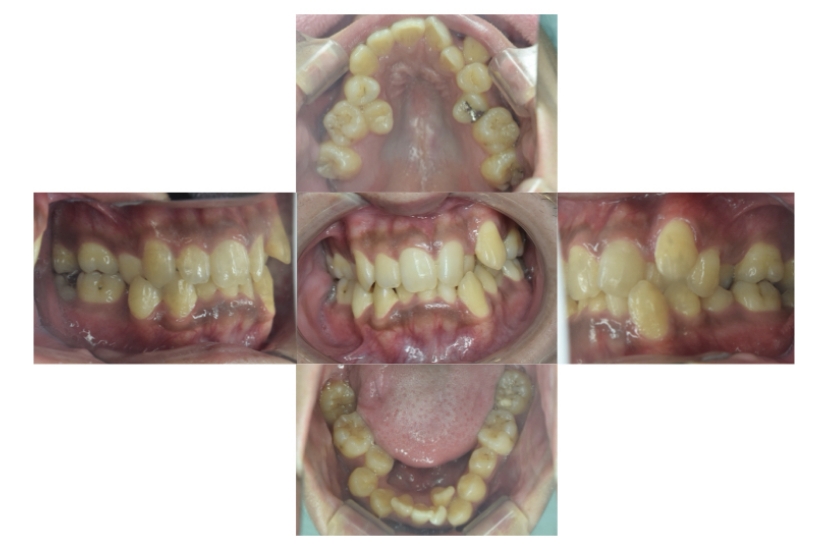

症例2

上下顎前突、叢生

抜歯

ブラケット矯正

上下顎前突、叢生(上下出っ歯、上下の前歯のガタガタ)のケースです。

装置はラビアル(上下表側)で、上下顎の小臼歯を4本抜歯を行っています。抜歯したスペースを使って、上下の前歯の後方移動と叢生(ガタガタ)の改善を行っています。

主訴 前歯のガタガタと口元がでているのが気になる。

年齢・性別 30歳 女性

お住まいの地域 東京都大田区

治療方針 抜歯スペースを利用して上前歯の叢生(ガタガタ)と口元突出の改善

抜歯部位 上下顎左右第一小臼歯

使用装置 ラビアル(上下表側)、顎間ゴム

治療期間 1年11か月

治療回数 13回

リテーナー クリアリテーナー

BEFORE

AFTER